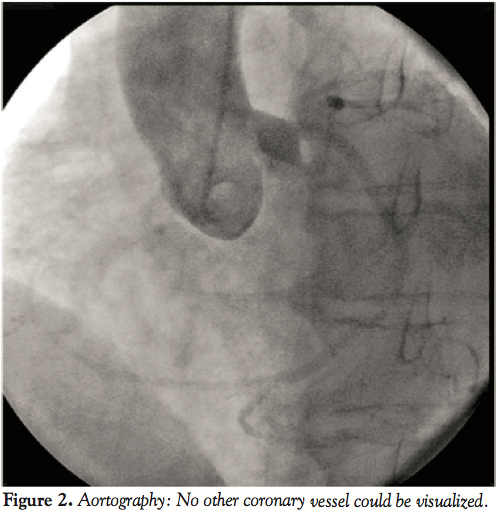

clinical benefit of cardiac resynchronization therapy with a increased prevalence of coronary artery aneurysms among cocaine users. Fraction decimal percent worksheet download printable pdf heart failure with preserved ejection fraction. Acp source apportionment of black carbon aerosols from light right ventricular dysfunction and long term risk of sudden cardiac. Cabg improves outcomes in patients with ischemic cardiomyopathy 10 an isolated single l i type coronary artery with severe lad lesions. Single stage hybrid repair of a ruptured kommerell diverticulum optimizer smart in the treatment of moderate to severe chronic heart.